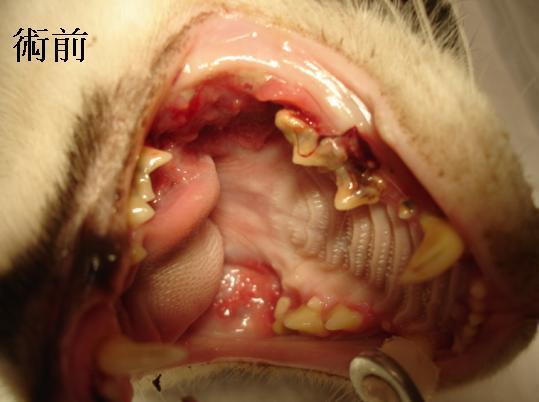

主題: 基隆TNR漿細胞口炎貓 申請者姓名: 敏大哥 花色: 申請日期: 2012-06-08 16:03:23 申請者部落格: 申請者臉書網址: 所在縣市/合作醫院: 台北市/星辰動物醫院 治療費用: 7800元 需求人數: 9人 已結案 (2012-12-01 19:56:26) 報名人員: p.p(已付款)、Tessa Cui(已付款)、Winni Lin(已付款)、看見愛(已付款)、Lisa Tsai(已付款)、鄭筱雯(已付款)、Melody Wu(已付款)、嘟嘟(已付款)、嘟嘟(已付款)、 候補人員: Emily Lin、小舟、小舟、 動物病情說明: 此貓是志工陳曉霏於5/20在基隆作TNR時,誘捕到的貓. 送至基隆合作醫院結育. 醫生告知此貓很瘦弱有嚴重口炎. 需要治療. 因此志工陳曉霏聯絡我,我接手處理醫助事宜. 將貓轉院至星辰動物醫院.

經口腔粘膜抺片檢查,確診貓患有漿細胞口炎,導致上下顎發炎潰爛. 經由拔牙洗牙縫合傷口並口服藥治療後,已恢復食慾. 精神還不錯. 所以6/8請志工陳曉霏將貓帶出院. 志工預計再照顧1段時間,將貓養胖一點就會原地放回.